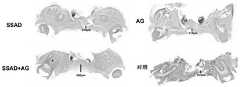

.本发明使用了40只(8-12周)、平均体重为200-220g的雄性Sprague-Dawley(SD)大鼠,并通过腹腔注射链脲佐菌素(streptozotocin,STZ,60mg/kg)诱导2型糖尿病。在注射STZ后1周,只有血糖水平高于≥250mg/dL的大鼠被纳入后续研究。硬腭粘膜损伤的诱导方法如First及其同事所述(参考文献51)。简言之,所有的动物都用1%戊巴比妥钠(30mg/kg)腹腔注射麻醉。然后,用开睑器(blepharostat)打开口腔,并用碘酒和75%乙醇对腭部粘膜消毒。接着,用一次性活检穿孔器(直径=3mm)在大鼠腭部(位于中间)形成全层硬腭粘膜缺损。所有动物被随机分为以下四组,并根据其组别(n=10)处理(这些处理每天重复进行):. The present invention used 40 (8-12 weeks) male Sprague-Dawley (SD) rats with an average body weight of 200-220 g, and induced by intraperitoneal injection of streptozotocin (STZ, 60 mg/kg). Type 2 diabetes. Only rats with blood glucose levels above ≥250 mg/dL at 1 week after STZ injection were included in the follow-up study. Hard palate mucosal lesions were induced as described by First and colleagues (ref. 51). Briefly, all animals were anesthetized with 1% sodium pentobarbital (30 mg/kg) intraperitoneally. Then, the oral cavity was opened with a blepharostat, and the palatal mucosa was disinfected with iodine and 75% ethanol. Next, a full-thickness hard palate mucosal defect was created in the rat palate (in the middle) using a disposable biopsy punch (diameter = 3 mm). All animals were randomly divided into the following four groups and treated according to their group (n=10) (these treatments were repeated daily):

-对照组:空白对照,未使用任何处理- Control group: blank control without any treatment

-AG组:AG(0.4mg/部位)-AG group: AG (0.4mg/site)

-SSAD组:SSAD水凝胶(每个部位,5mg SSAD粉末)- SSAD group: SSAD hydrogel (5 mg SSAD powder per site)

-SSAD+AG组:装载AG的SSAD水凝胶(每个部位,5mg SSAD粉末+0.4mg AG)-SSAD+AG group: AG-loaded SSAD hydrogel (5 mg SSAD powder + 0.4 mg AG per site)

.在本发明的整个实验期间,没有观察到异常的生理症状。与其他两组相比,用SSAD和装载AG的SSAD(SSAD+AG)处理的小鼠显示出较少的出血(图4a)。此外,经典的肝脏损伤-止血模型(图14)表明,SSAD可以有效地粘附到伤口部位,密封并止血(图15)。如图4b和表2所示,在术后4天,SSAD+AG组(61.2±4.3%)、AG组(55.1±9.8%)和SSAD组(56.8±13.1%)的动物伤口闭合率显著快于对照组(37.7±9.9%),其中SSAD+AG组愈合最快。在术后8天,SSAD+AG组的动物的伤口闭合率(78.3±5.1%)仍显著高于对照组(53.7±15.3%)。在术后18天,SSAD+AG组的伤口几乎完全愈合,平均伤口闭合率为97.4±3.3%,其也高于对照组(88.3±9.8%)、SSAD组(92.5±7.1%)和AG组(92.5±9.0%),且SSAD+AG组与对照组之间的差异显著(P<0.05)。因此,SSAD+AG在相对较短的时间内极大地加快口腔粘膜缺损的愈合。. During the entire experimental period of the present invention, no abnormal physiological symptoms were observed. Mice treated with SSAD and AG-loaded SSAD (SSAD+AG) showed less bleeding compared to the other two groups (Figure 4a). Furthermore, the classic liver injury-hemostasis model (Figure 14) demonstrated that SSAD can effectively adhere to the wound site, seal and stop bleeding (Figure 15). As shown in Figure 4b and Table 2, the wound closure rate of animals in SSAD+AG group (61.2±4.3%), AG group (55.1±9.8%) and SSAD group (56.8±13.1%) was significantly faster at 4 days after surgery Compared with the control group (37.7±9.9%), the SSAD+AG group healed the fastest. Eight days after the operation, the wound closure rate of animals in the SSAD+AG group (78.3±5.1%) was still significantly higher than that in the control group (53.7±15.3%). At 18 days after surgery, the wounds in the SSAD+AG group were almost completely healed, with an average wound closure rate of 97.4±3.3%, which was also higher than that of the control group (88.3±9.8%), SSAD group (92.5±7.1%) and AG group (92.5±9.0%), and the difference between the SSAD+AG group and the control group was significant (P<0.05). Therefore, SSAD+AG greatly accelerates the healing of oral mucosal defects in a relatively short period of time.